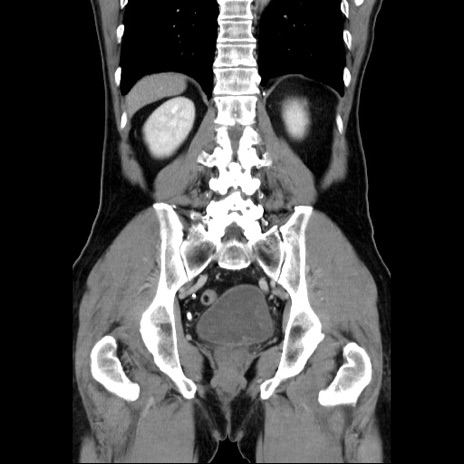

症例34(冠状断像)

【症例】60歳代 男性

【主訴】右鼠径部膨隆

【現病歴】1年程前より右鼠径部膨隆あり。自己にて還納可能だったため放置していた。3時間前より右鼠径部の脱出を認め、還納困難となり受診。

【既往歴】高血圧

【身体所見】右鼠径部に小児頭大の膨隆あり。弾性硬であり、用手還納は困難。左鼠径部にも膨隆を認める。脱出はなし。